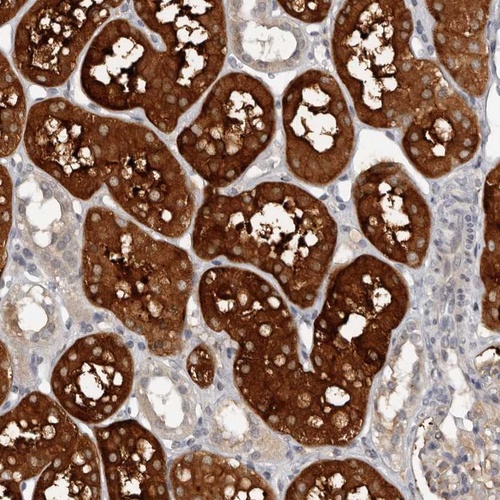

Immunohistochemical staining of human kidney shows strong cytoplasmic positivity in tubules.